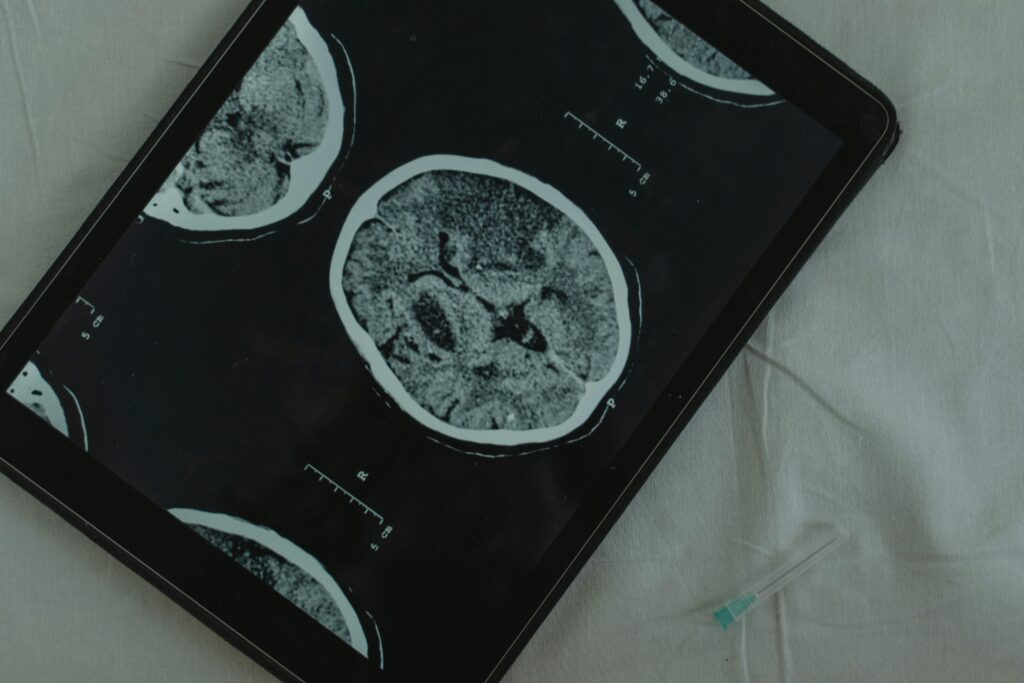

🧩 బ్రెయిన్ లో వేస్ట్ కెమికల్స్ ఎలా తయారవుతాయి?

బీటా అమైలాయిడ్ ప్రోటీన్లు → మెదడు సెల్స్ కి హానికరం

ఫ్రీ రాడికల్స్ → oxidative stress వల్ల ఏర్పడతాయి

టాక్సిన్స్ → సరైన క్లీనింగ్ లేకపోతే బ్రెయిన్ లో నిల్వ అవుతాయి

👉 ఇవి ఎక్కువైతే:

Concentration తగ్గుతుంది

మతిమరుపు పెరుగుతుంది

ఆందోళన, డిప్రెషన్ వస్తాయి

వృద్ధాప్యంలో మెదడు సమస్యలు రావచ్చు